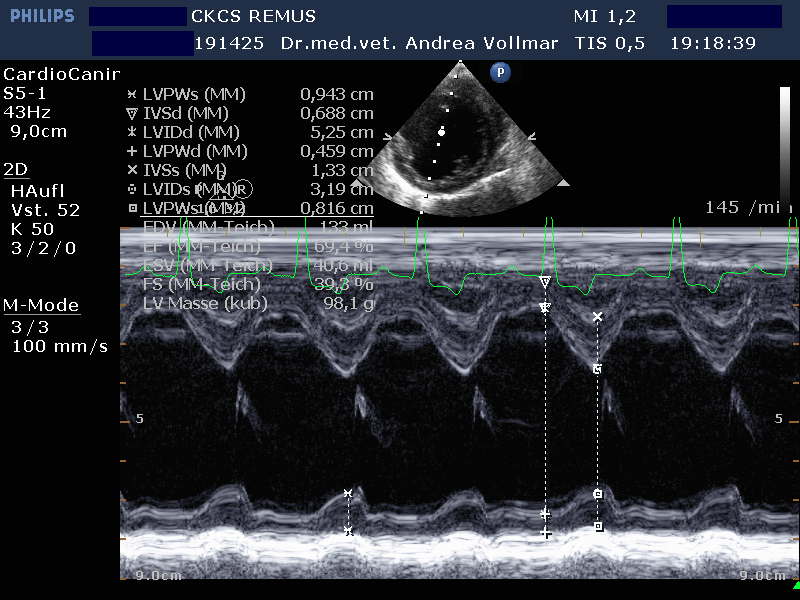

Am sichersten kann die Größe der einzelnen Herzabteilungen und der Schweregrad einer AV-Klappeninsuffizienz mit Hilfe der Echokardiografie beurteilt werden. Die Messung der Vorhofgröße vorzugsweise im 2D-Bild korreliert zuverlässig mit dem Ausmaß der MI. Mittels verschiedener Doppler- und Farbdoppler-Analysemethoden kann die Größe der Lücke in der Mitralklappe bestimmt und das regurgitierte Blutvolumen ermittelt werden.

Die degenerative Mitralklappeninsuffizienz (MI) stellt beim Hund die Hauptursache für ein kongestives Herzversagen und kardial bedingten Tod dar. Im Krankheitsverlauf vergrößert sich mit zunehmender Schwere der Klappeninsuffizienz zunehmend der linke Vorhof und das diastolische Ventrikelvolumen nimmt zu, während das systolische Ventrikelvolumen erst mit nachlassender Kontraktilität bei Entwicklung einer Volumenüberlastungskardiomyopathie zunimmt. Bei kleineren Hunden unter 15 kg Körpergewicht ist dies oft erst später im Krankheitsverlauf der Fall, bei größeren Hunden über 15 kg hingegen häufig früher.

Nach derzeitigem Kenntnisstand ist bei MI eine Medikation immer erst dann sinnvoll, wenn bereits eine Herzvergrößerung vorliegt.